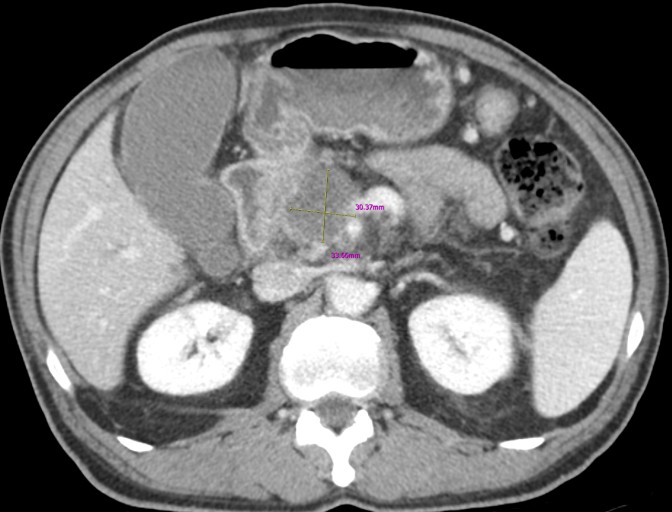

췌장염 증상 황달 + 진한 소변 + 연·회색 변(담즙 배출 장애 신호)

췌장과 담도는 해부학적으로 가깝습니다. 염증/부종이나 담석이 담즙 흐름을 막으면 피부·눈 흰자 노랗게(황달), 소변 짙은 갈색, 변이 옅거나 회색으로 바뀔 수 있습니다